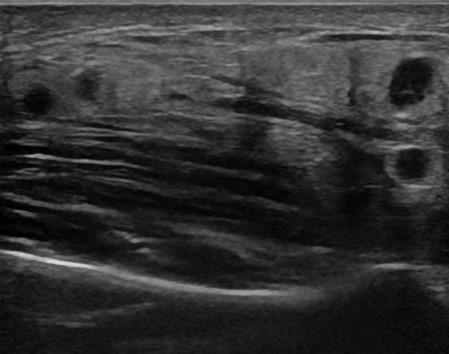

Viêm tuyến nước bọt

» Thông tin: Nam giới – 16 tuổi.

» Lâm sàng: Sưng đau vùng góc hàm từng đợt.

# Viêm tuyến nước bọt dưới hàm mạn tính.